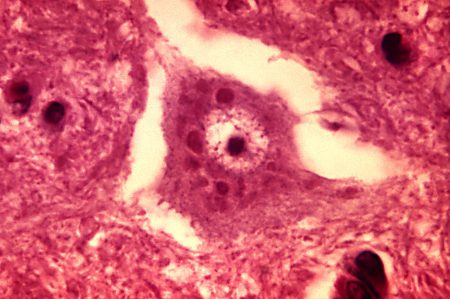

- There is no way to test for the infection in a live animal. The only way to test definitely for the disease is via examination of the brain tissue of a dead vector.